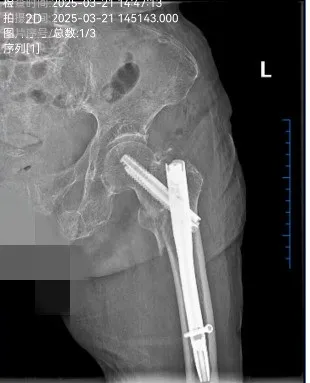

骨科團隊憑借豐(fēng)富的臨床經驗和先進的技術手(shǒu)段,采用國際領先的Intertan髓內釘係統,通過微創小切口完成複位固定。該係統具有雙螺釘設計,形成(chéng)更強的抗旋轉能力,提供更高的穩定性;同時利用滑動(dòng)加(jiā)壓(yā)原理,促進骨痂形成,顯著減少術後並發症的發生。手術(shù)僅曆時30分鍾,術中出血不到50毫升,極(jí)大地降低了(le)手術風險。

術後,團隊立即啟動加速康複(fù)外科(ERAS),采取了一係列預防措施,包括深(shēn)靜脈血栓、感染、壓瘡等並發症的防控,並(bìng)為患者量身定製了營養管(guǎn)理方案。護理團隊提供了全方位(wèi)、全(quán)天候的優質護理服務,幫(bāng)助患者快速恢複。術後24小時內,陳奶奶便從(cóng)臥(wò)床狀態恢複到自主活動,重新拾起了生活的(de)信心和尊嚴。